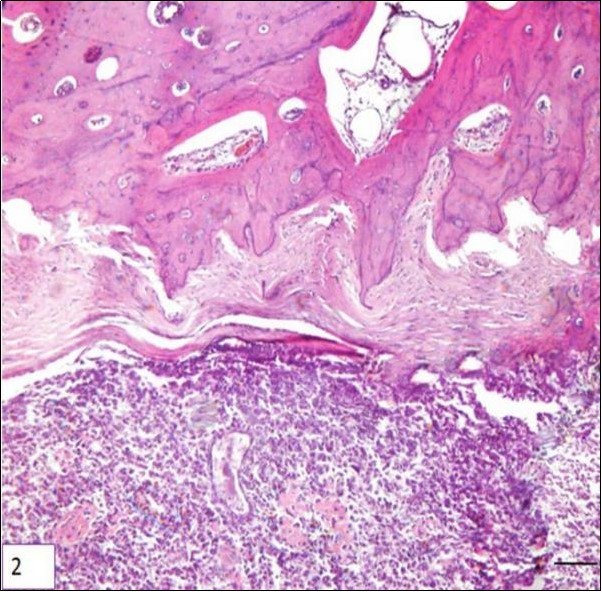

Two types of periosteal osteosarcoma have been described in dogs. The first is an aggressive tumor with the same histopathological characteristics and biological behavior of central osteosarcoma. Such tumors may actually be central osteosarcomas that arose in the cancellous bone of the metaphysis of a long bone and for some undetermined reason developed an eccentric growth pattern. The second type of periosteal osteosarcoma is similar to the description found in humans. Only two reports have been described this tumor in the metaphyseal surface of long bones rather than the diaphyseal surface in humans. Both of them, produce dense bone matrix and none of the dogs had metastasis after limb amputation Figure 217.

Figure 2.Photomicrography of a sample of canine bone (tibia) showing neoplastic mesenchymal proliferation, originated in bone cells, HE. Periosteal array of tumor cells, bar 200 μm.